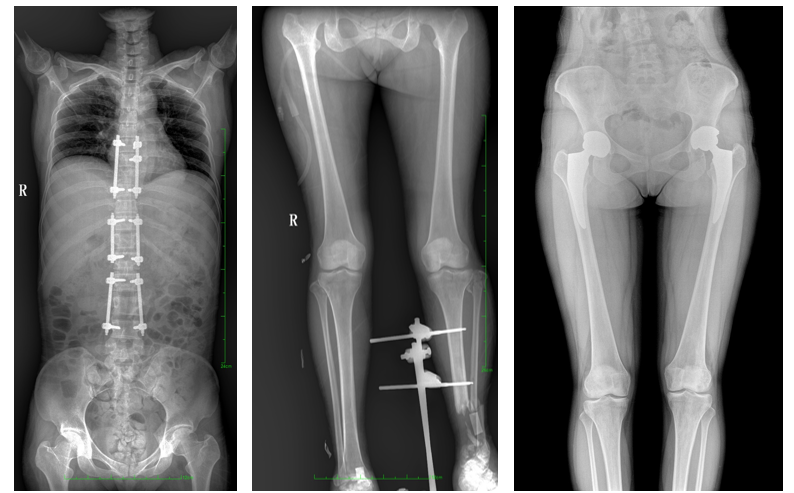

全脊柱一次成像 不拼接

17"*34"有效視野,是市面大尺寸平板的2倍,一次成像不拼接。相較于多張攝影再軟件拼接的DR設備,PLX8600解決了拼接圖像存在密度不均勻,拼接處圖像配準和放大效應等問題,給臨床帶來了真正的大視野影像解決方案,高清畫質(zhì),準確成像不失真,可一次性覆蓋全脊柱或雙下肢影像。PLX8600大視野平板動態(tài)DR攝影速度快,患者可以更快的完成檢查,且單次攝影輻射劑量是常規(guī)多張攝影再軟件拼接DR的1/2或1/3,低劑量給患者更多關(guān)愛。